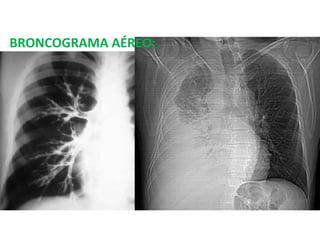

BRONCOGRAMA AEREO

BRONCOGRAMA AÉREO: